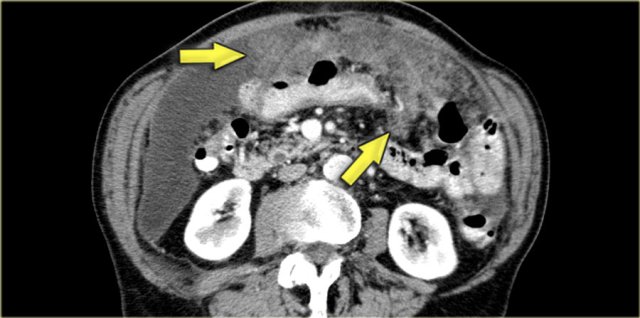

On the left another case of pseudomyxoma peritonei.

There is hardly any scalloping of the liver.

Notice the thickened falciform ligament.

There is a mucocele of the appendix (arrow).

This finding is only rarely seen.

There is compression of the mesentery resulting in a thickened cake-like hyperdense mesentery (arrow).

There are also some calcifications.